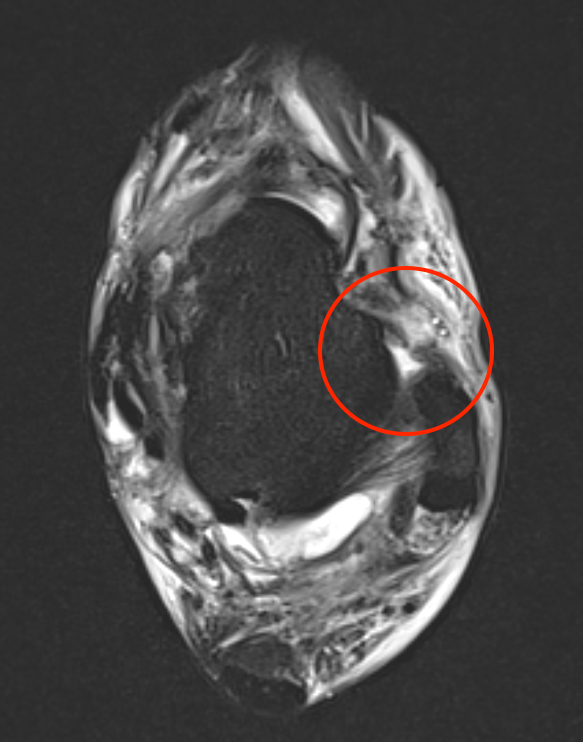

MRI

ATFL tear